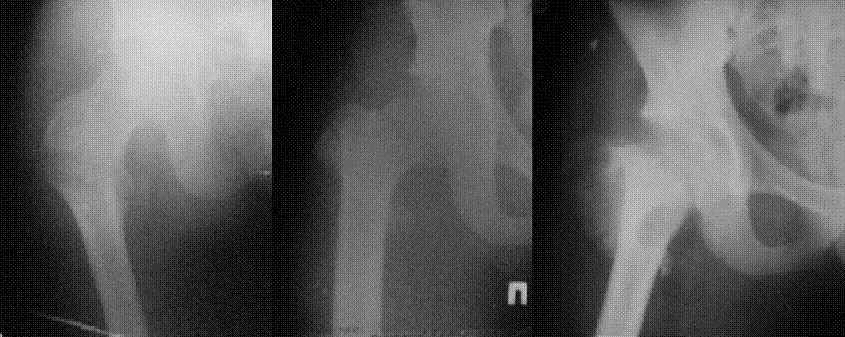

Уважаемые коллеги! Нужен совет. Больной Х., 21 год, ДЗ: ложный сустав вертельной области

правого бедра. Травма 8 мес. назад, ДТП, получил закрытый межвертельный перелом правого

бедра. Лечился в городской больнице одного из городов-спутников г. Караганды скелетным

вытяжением в течение 3 недель, затем кокситной гипсовой повязкой 2 мес.

В настоящее время имеется укорочение конечности на 7 см, умеренная

боль в вертельной области; ходит без костылей, полностью нагружая

больную конечность, при нагрузке отмечается смещение дистального

отломка проксимально примерно на 1,0 см.; объем движений в коленном

суставе сохранен; при пальпации отломков боли нет, умеренная

патологическая подвижность.